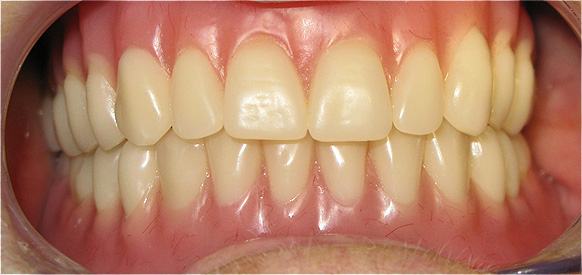

Resultado de colocação de implante dentário na Clínica São Filinto

A colocação de implantes dentários de titânio é, atualmente, a melhor forma de substituir os dentes ausentes, pois não só lhe devolve a estética dentária perdida, como também a sua função mastigatória.

A utilização de novos materiais nas coroas implanto-suportadas, como o zircónio, e as novas técnicas laboratoriais avançadas, em conjunto com a utilização de softwares especializados na construção das coroas dentárias, aumenta ainda mais a estética dentária porque confere ao dente um aspeto muito natural.